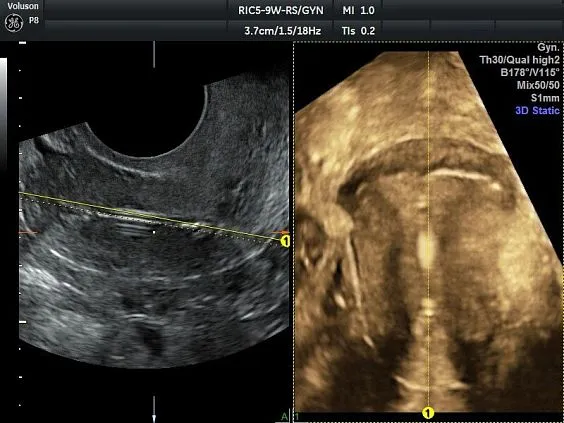

Клинические изображения

Несмотря на демократичную цену, Voluson P8 обеспечивает изображение экспертного уровня, включая поддержку 3D/4D-визуализации, что делает его востребованным в акушерстве и гинекологии. Он построен на платформе Voluson Core Architecture, которая гарантирует высокое качество двухмерной и трёхмерной визуализации, а также стабильную производительность при рутинных исследованиях.

Voluson P8 одинаково уверенно справляется как с задачами в сфере женского здоровья (оценка развития плода, диагностика патологий малого таза), так и при сканировании сердца, сосудов, органов брюшной полости и поверхностных структур. Аппарат поддерживает современные технологии обработки изображения: HD-Flow™, Speckle Reduction Imaging (SRI), CrossXBeam™, что позволяет получить максимально чёткие и информативные данные даже в сложных клинических условиях.

Простота получения 3D-изображений

Визуализация в режимах 3D/4D позволяет исследовать дополнительные анатомические плоскости, повышая вашу уверенность в диагностике.

- Визуализация плоскостей недоступных для исследования при 2D-сканировании, для более точной диагностики.